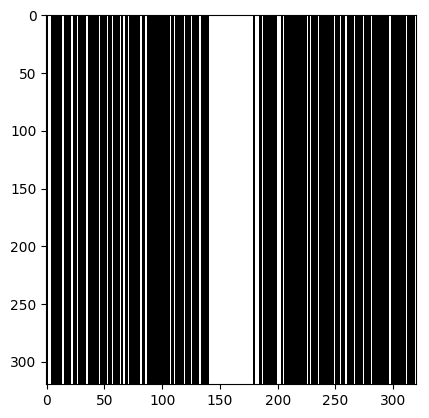

We consider the following two inverse problems: (i) Superresolution (SR), consisting of reconstructing a sharp image from measurements containing only the central low frequencies obtained by using the mask as in Fig. 2 (a & c); and (ii) Dealiasing, in which the obtained mask results in an aliasing artifact due to a coarser sampling in the phase-encoding direction. We use the masks displayed in Fig. 2(b & d). The inverse problem consists of restoring a finer sampling grid in the phase-encoding direction. Throughout the paper, we denote the experiments specifying the task name (one of the two tasks above) and the acceleration factor.

| (a) SR 4 | (b) Dealiasing 4 | (c) SR 8 | (d) Dealiasing 8 |